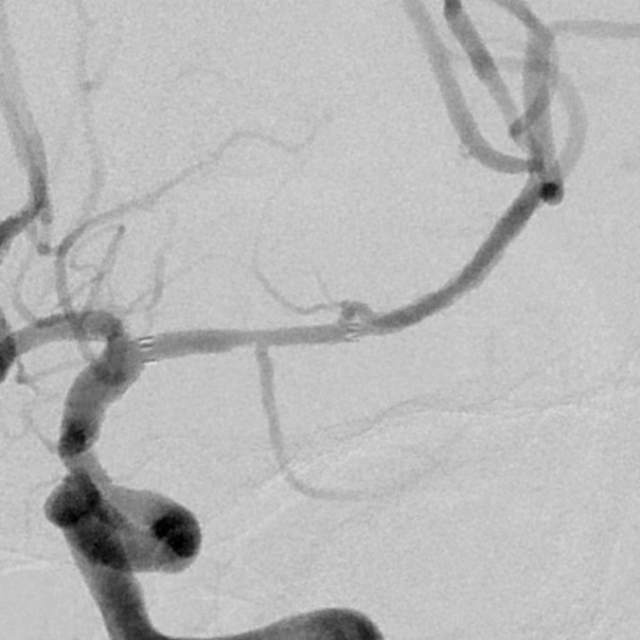

​2、第二个患者:我们给予一期外科干预后,一个月后检查发现,狭窄的部位和术后即刻相比是稳定的,二期安全的植入支架,血流完全恢复正常,顺利出院;

术前

术后即刻

术后一个月随访稳定,给予支架植入,血流恢复正常,分支血管保留良好